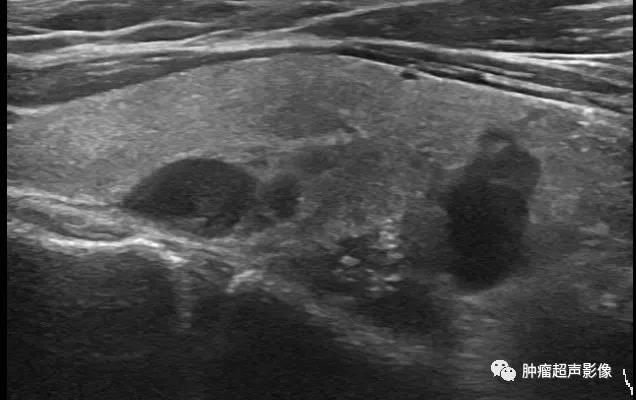

慢性肾脏疾病,血PTH升高,左侧2个(上图)、右侧1个(下图)增大的甲状旁腺腺体,呈边界清的低回声,与甲状腺分界清晰,其中两个内见钙化。